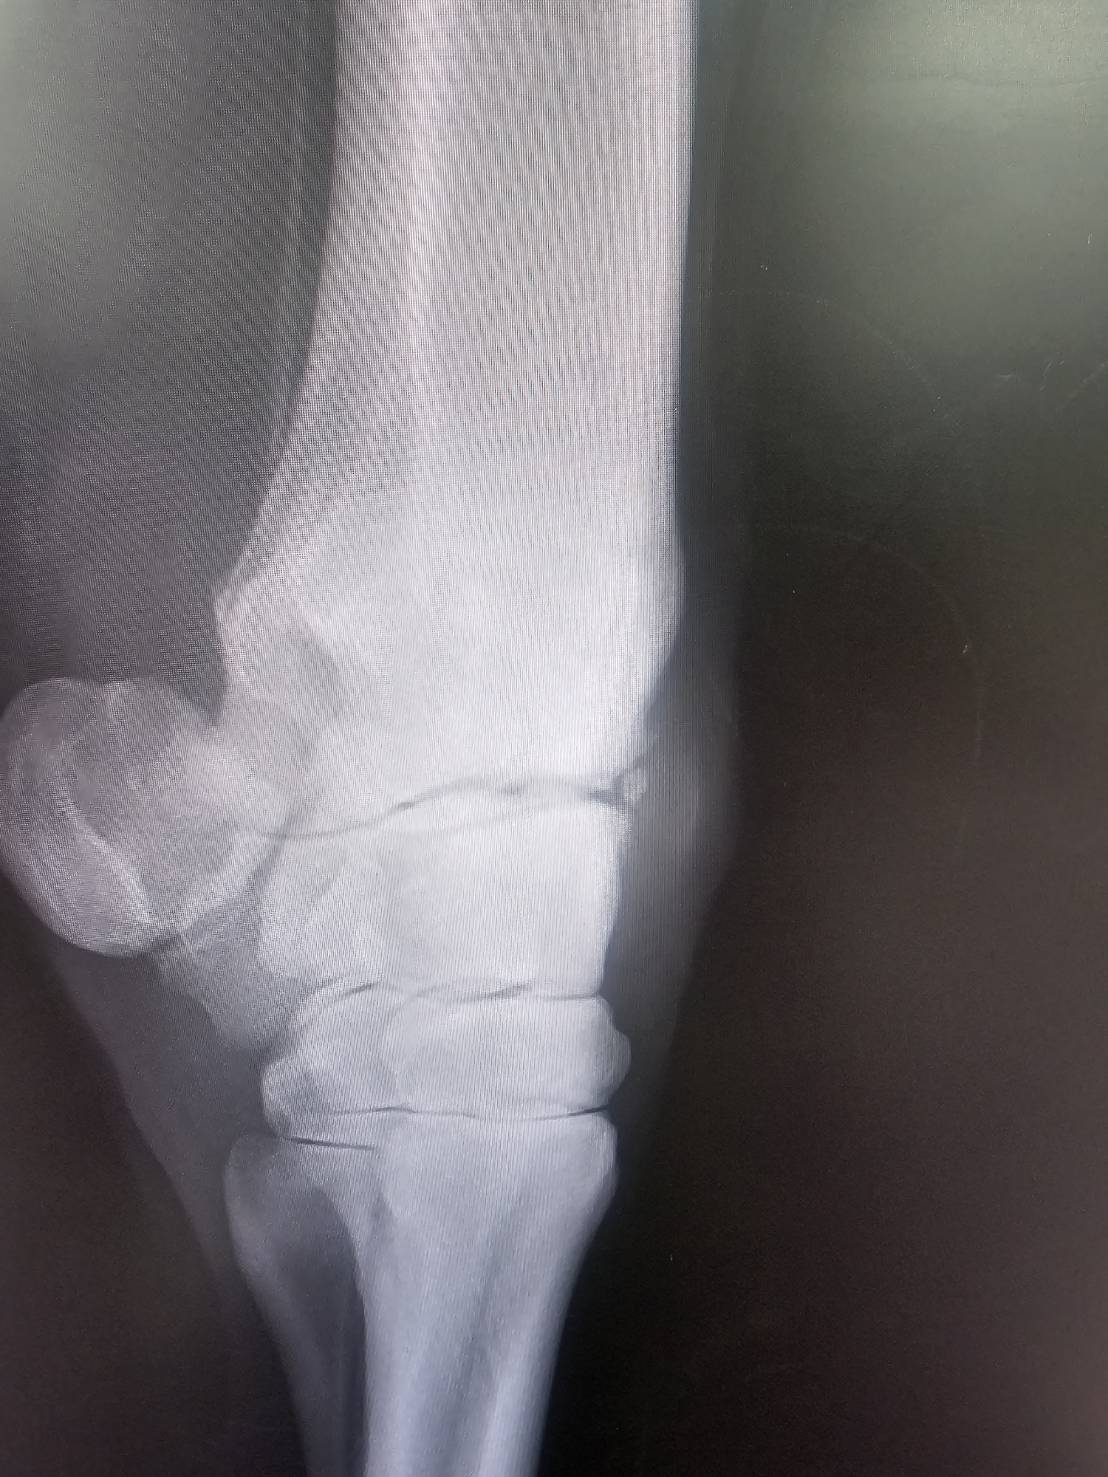

本馬は、美浦・中川公成厩舎から2024年10月20日の京都ダート1200mで馬体重500㎏でデビュー。16頭立ての14番枠からスタートを決めて4~5番手を追走すると、直線でメンバー3位タイの上がりを使い、逃げた勝ち馬から2秒1差、2着には0秒3差の3着に入ります。初戦からまずまずの手応えをつかんで迎えた中2週の東京ダート1400mでしたが、15頭立ての5番手から伸びを欠いて3秒0差の10着。レース後に右前肢の橈骨遠位端骨折発症が判明し(下記に詳細)、長期休養を余儀なくされます。

再転入初戦となった前走でしたが、右前肢の橈骨遠位端骨折を再発してしまいました。タイムオーバーの適用は除外となり、見舞金9号(競走中6カ月)が適用され、このタイミングでオークション出品となります。

※2026年2月21日の競走中、右橈骨遠位端骨折を発症。事故見舞金9号(競走中の事故により事故発生の日から6ヵ月以上出走できなくなった場合)の適用を受けています。なお、「タイムオーバーによる出走制限」の適用を除外されています。

※2024年11月10日の競走で、右橈骨遠位端骨折を発症。事故見舞金9号(競走中の事故により事故発生の日から6ヵ月以上出走できなくなった場合)を受給しています。